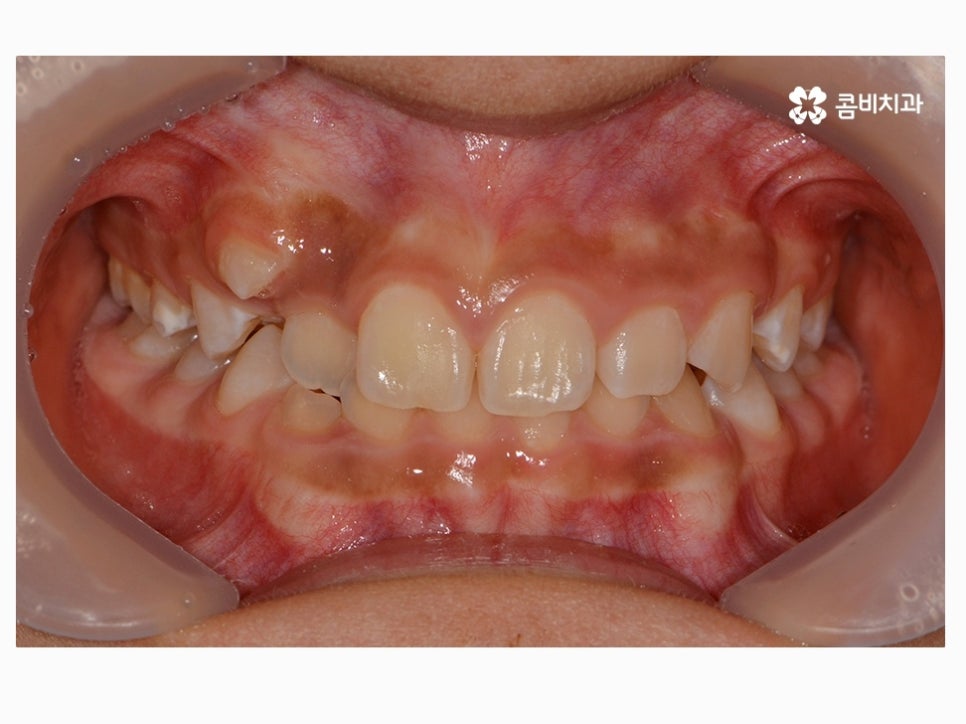

과개교합은 부정교합의 종류 중 하나라고 할 수 있으며

윗니가 아랫니를 정상보다 많이 덮고 있는 형태로 흔히 과개교합 혹은

피개교합으로도 불리고 있어요.

보통 윗니가 과도하게 돌출되어 있거나 치아의 크기가 큰 경우,

아랫니가 과하게 안쪽으로 들어가 있는 경우, 선천적으로 골격성 부정교합에

해당되거나, 이갈이 등 어금니에 과하게 힘이 가해지면서

마모되거나 치관의 길이가 짧아진 경우에

윗니가 아랫니를 덮고 있는 형태를 하게 될 수 있는데요.